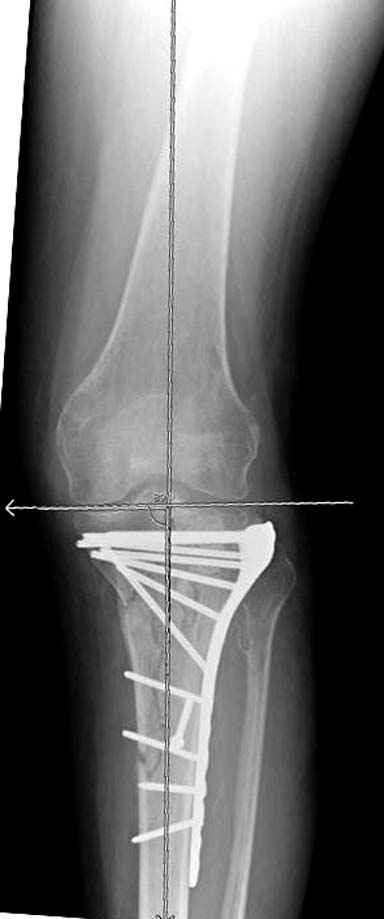

Отдельные переломы тибиал плато и перелом проксимальной трети большеберцовой кости отличаются от переломов тибиал плато с вовлечением диафиза. Здесь перелом тибиал плато типа Schatzker VI, полученный в результате высокоэнергетической травмы. Перелом метафиза образовал отрыв суставной поверхности от диафиза с вовлечением медиального и латерального мыщелков. Двухмыщелковые переломы из-за укрочения опасны развитием компартаментального синдрома, повреждением латерального мениска и связок.

На вашем место я бы подождал с фиксацией до готовности кожных покровов, и за это время можно было подобрать соответствующий фиксатор, т.е более длинная пластина снаружи и медиальная пластина на апексе перелома как подпорка. Здесь приемлем как раз минимальный доступ.

Имеющаяся импрессия не потребовала пластики - достаточным оказалось поднять отломок

Если там действительная импрессия, пустое место без структуральных заполнителей, кость или синтетические материалы, не восстановится, а образуется коллапс, и ось конечности поведет после нагрузки. Кроме того там возможно "болт стяжка"?, в медиальной стороне выступает за кортекс, можно было укоротить! Потом создается впечатление, что не соответствуют мыщелки большеберцовой и бедренной костей? Покажите снимок.

Здесь пару случаев для сравнения,...в первых 1-4 слайдах метод фиксации одним фиксатором, как видно после 8 месяцев сохранилась ось. С 5 по 9 вариант двумя пластинами...